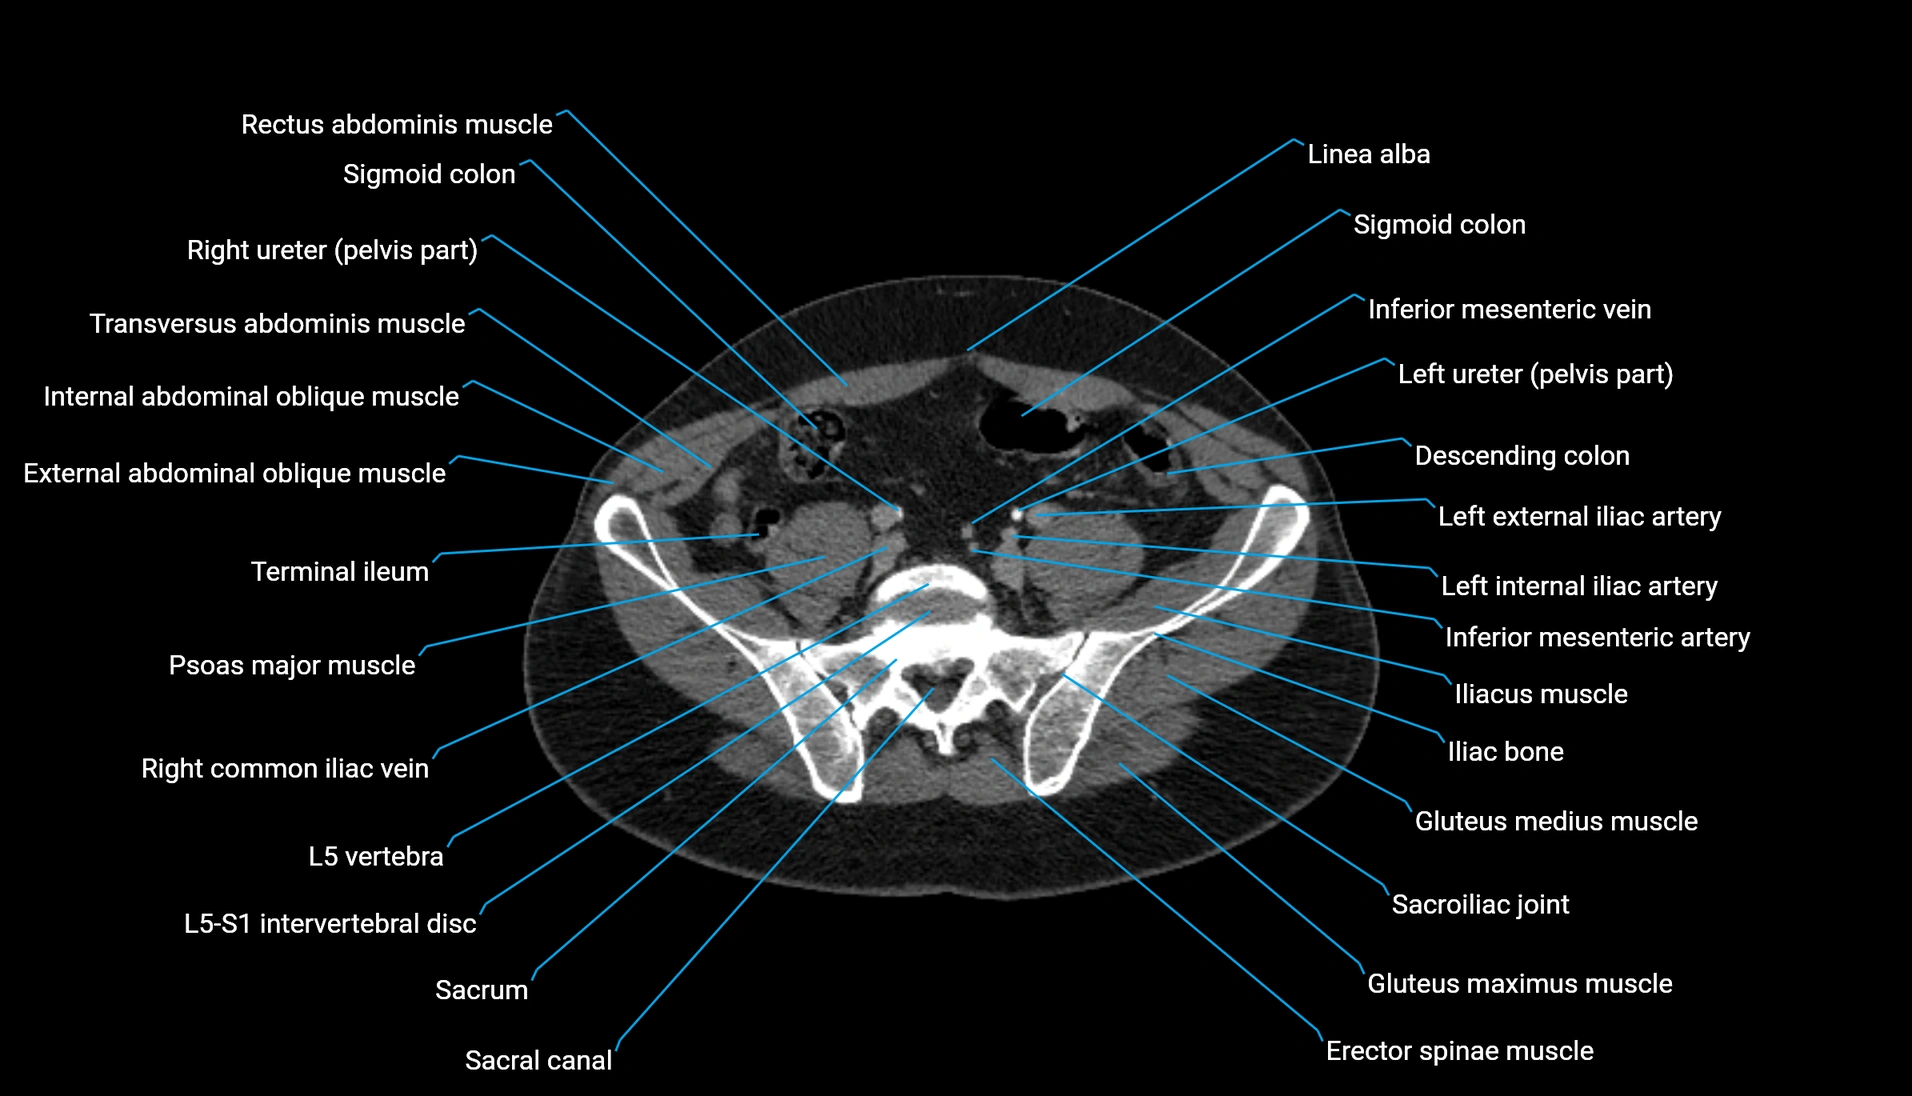

CT Appearance

Non-contrast CT:

-

Demonstrates cortical bone of acetabular rim in excellent detail

Detects fractures, dysplasia, retroversion, or bony overcoverage (pincer impingement)

3D reconstructions used in preoperative hip surgery planning

CT VRT 3D image

CT image